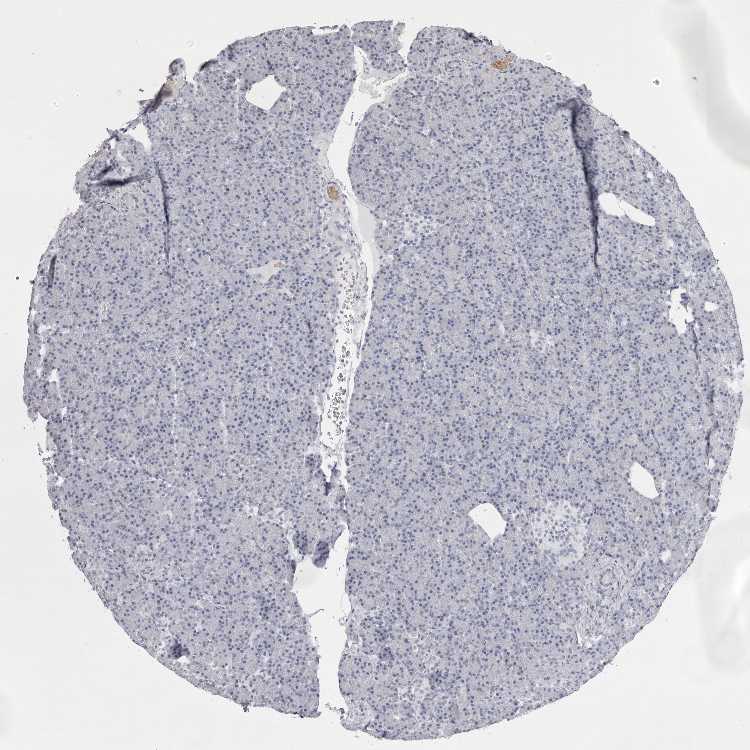

PANCREAS - Antibody stainingi

Antibody staining in the annotated cell types in the current human tissue is reported as not detected, low, medium, or high, based on conventional immunohistochemistry profiling in selected tissues. This score is based on the combination of the staining intensity and fraction of stained cells.

Each image is clickable and will lead to virtual microscopy that enables deeper exploration of all samples and also displays staining intensity scores, fraction scores and subcellular localization as well as patient and tissue information for each sample.

Antibody HPA028048Antibody HPA028253Antibody CAB016193Antibody CAB037246

Exocrine glandular cells MediumNot detectedLowLow

Pancreatic endocrine cells Not detectedNot detectedNot detectedNot detected